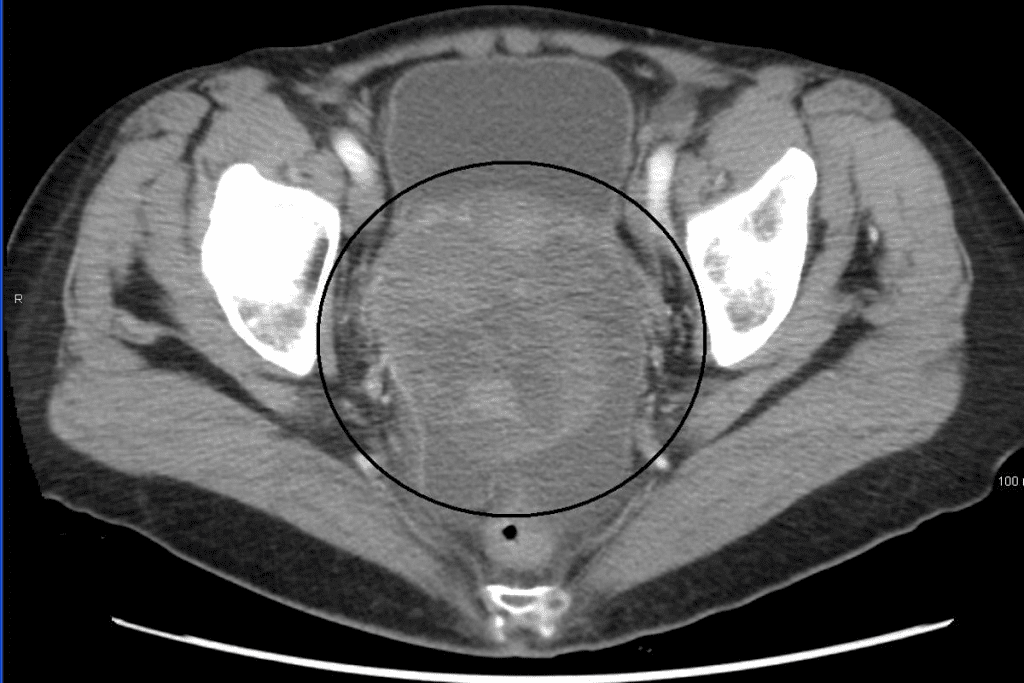

Imaging Techniques (Ultrasound, CT, MRI)

Imaging tests like ultrasound, CT scans, and MRI help see the ovaries and find problems. Ultrasound is often the first choice because it’s non-invasive. It can spot ovarian masses. CT and MRI scans give more detailed images and check if the cancer has spread.

Limitations of Imaging Techniques: These tests can spot masses but can’t always say if they’re cancer. Small tumors might not be found.